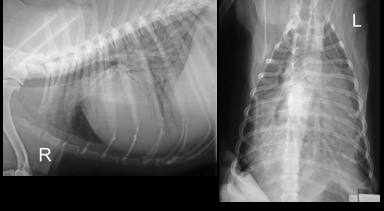

• DV and lateral

• DV view is rotated which may affect interpretation (care with cardiac silhouette). Cant tell if inspiratory

• Lateral is inspiratory and minimal rotation. Good centre. Collimation etc.

• Cardiac enlargement – large CS. Very tall - Dorsally displaced trachea

• Lung pattern – Alveolar (air Broncho grams, increase opacity, obliteration etc.) caudually. Cr lung lobe has a little increase in opacity but not as affected as much

• Lateral view – lung lobe alveolar pattern and some air bronchograms predominately caudally. Cn see edges of diaphragm, BV and CS. Not all an alveolar pattern as you wouldn’t be able to see these). So there is a part interestital pattern too.

• Bonsell: The whole thorax is affected

• When drawing a line from the trachea bifurcation to the apex there is not an even chamber distribution

• Around 3.5 intercostal spaces width (should be 2.5 -3.5 on lateral)

• Height of the heart on the lateral view is more than 2/3 high at the level of the 5th rib

• Border obliteration of CS on DV and also cant see diaphragm

• Caudal margin is more caudal than it should be and straight – LEFT SIDE ENLARGEMENT

• Not that increased sternal diaphragmatic contact – so right side isn’t enlarged

• No real sign of plural disease

• Hard to assess vessels due to patterns